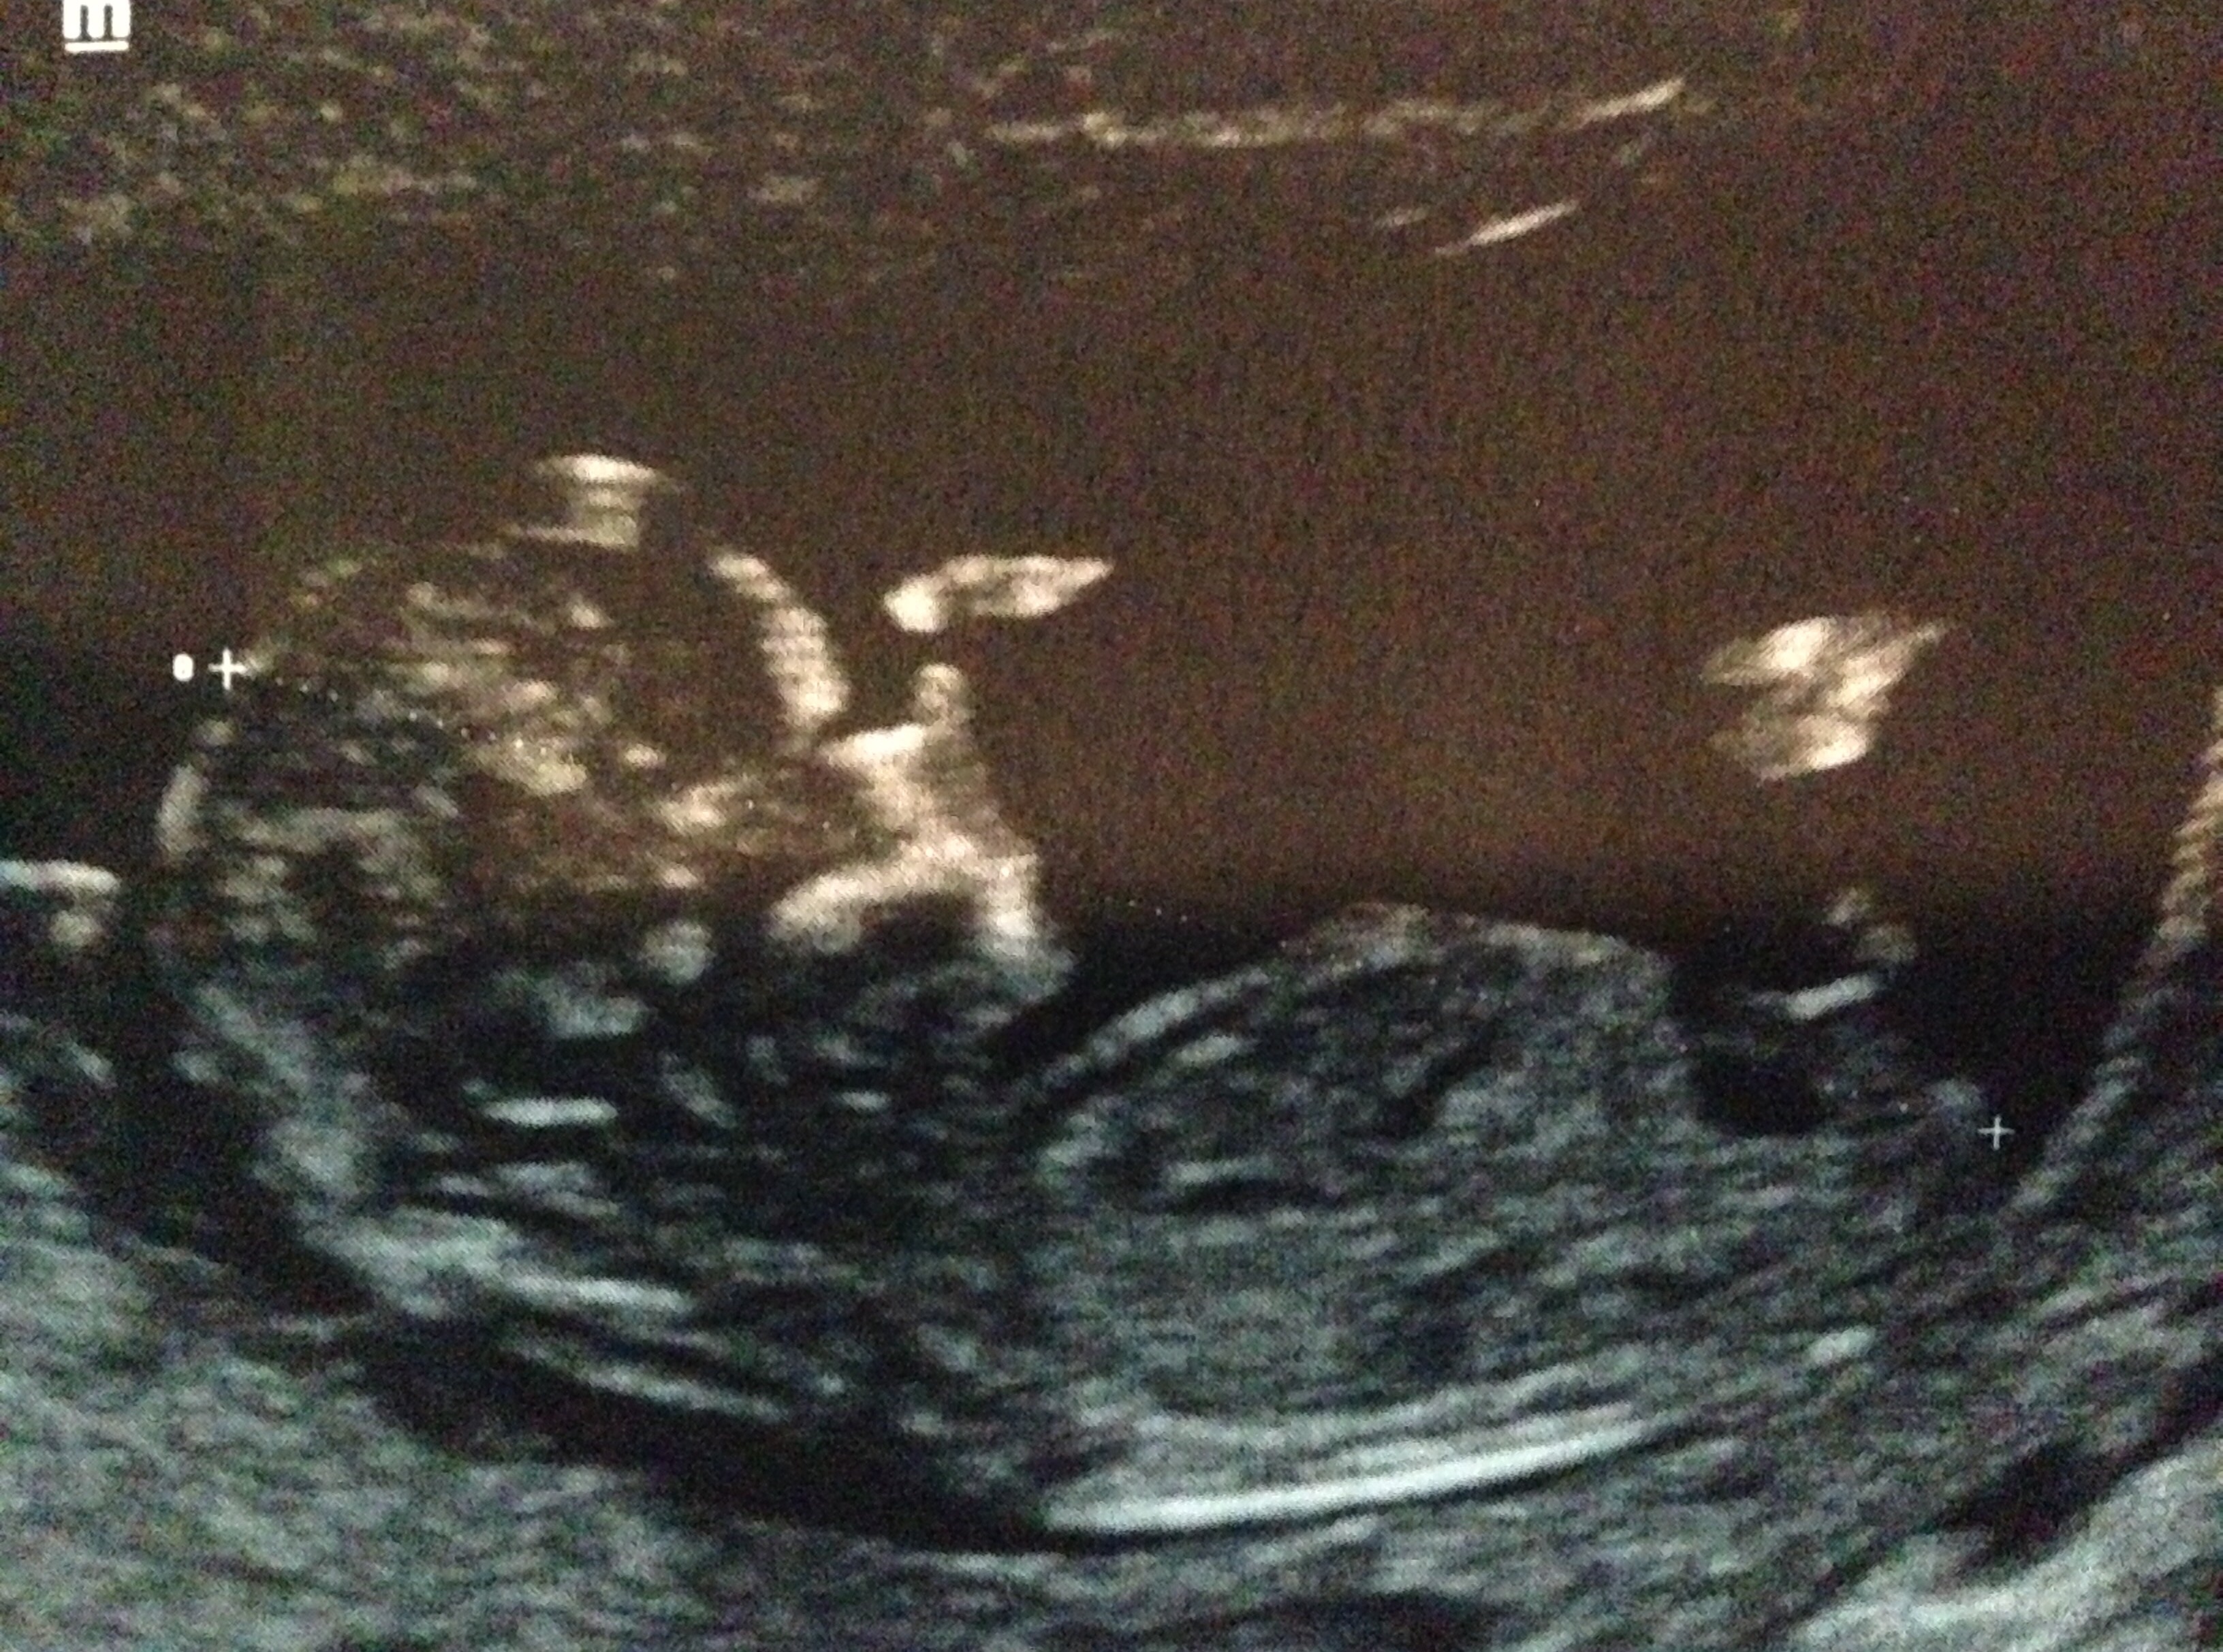

I am thinking boy. She is 12 weeks 4 days. Attachment 23692